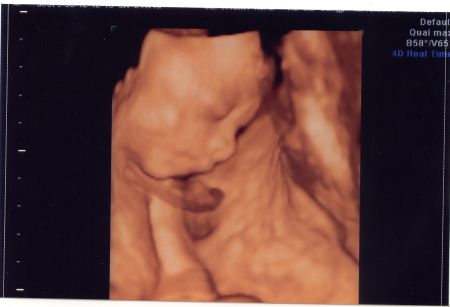

Sziasztok lányok!

Szerintetek most már bizti, hogy ki lakik a pocimban? :D

655 g és minden rendben. De állandóan takarta a kis arcát igy teljes képet nem sikerült róla csinálni. Kép Kép

Édes kis fütyikés!! Gratulálok!

Nagyon jók a képek!